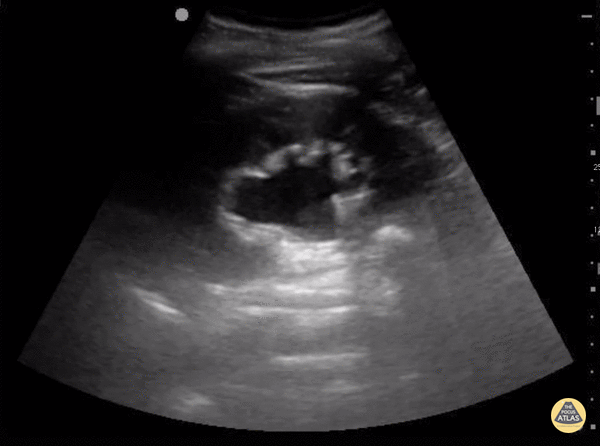

Renal/GU - Moderate Hydronephrosis

The degree of hydronephrosis is determined by a grading system. Grade 0 (none) means there's no dilation of the renal pelvis. Grade 1 (mild) means there's mild dilation of the renal pelvis without any dilation of the calyces. Grade 2 means there's moderate dilation of the renal pelvis that extends to a few calyces. Grade 3 (moderate) means the renal pelvis dilation extends to all the calyces. Grade 4 (severe) means there's extension of dilation to all the calyces with the addition of thinning of the renal parenchyma. In this clip, the renal pelvis calyces are dilated but there is no thinning of the renal parenchyma making this mild to moderate, grade 2. Sukh Singh, MD Caption by Matthew Riscinti, MD